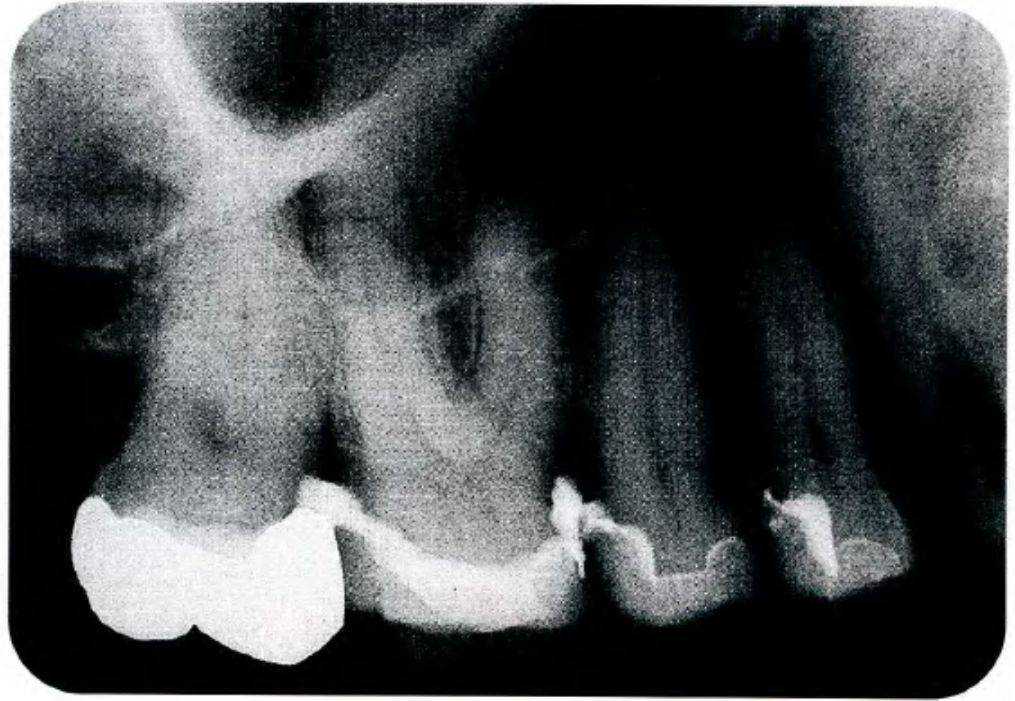

Рис. 2-24д. Керамические вкладки установлены в полости

Рис. 2-24И. Керамические вкладки установлены с помощью кончика ультразвуковой насадки Соноцем